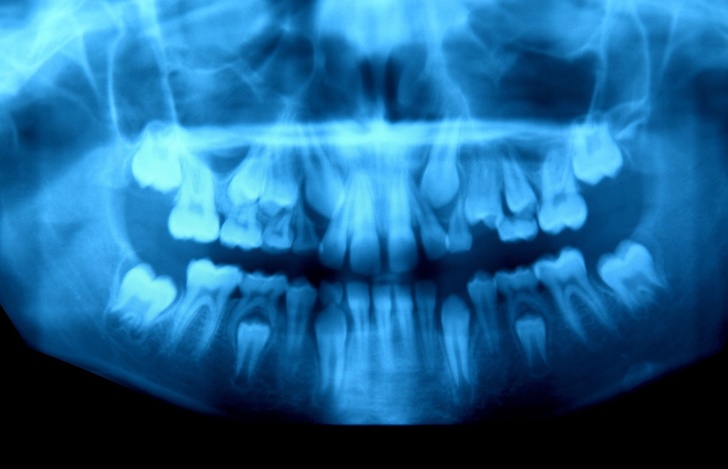

8. Čeľusť 10-ročného chlapca, ktorému pomaly vypadávajú mliečne zuby